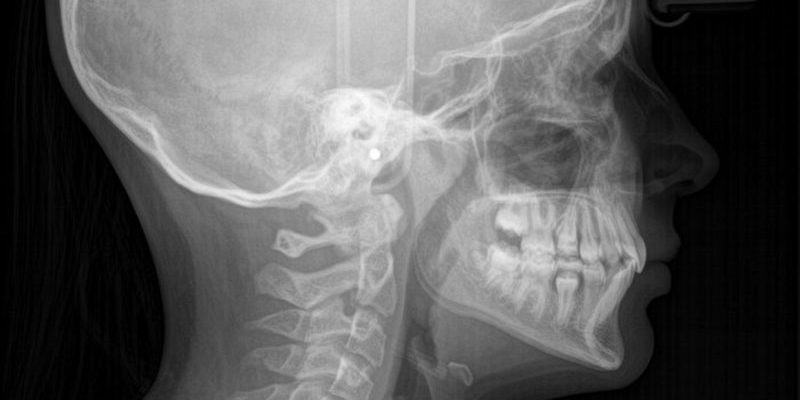

- una teleradiografia latero-laterale ed una postero-anteriore del cranio